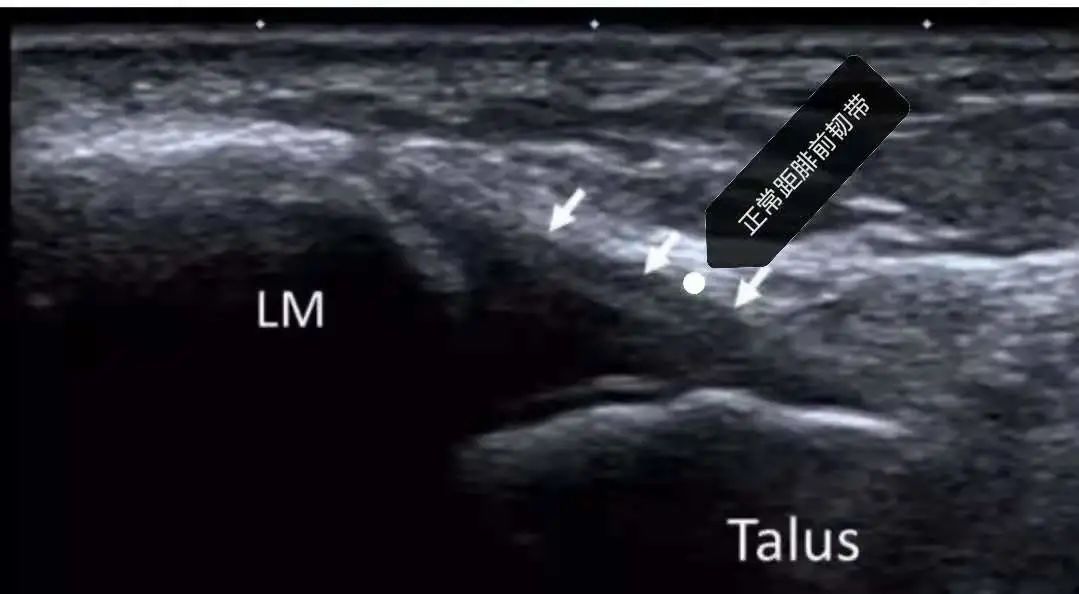

正常分歧韧带及跟骨前上突

分歧韧带损伤伴跟骨撕脱骨折

打篮球脚崴了,拍个x片提供骨折情况,踝关节超声能提供距腓前韧带、跟腓韧带、分歧韧带以及肌腱是否连续,断端位置,积液情况!